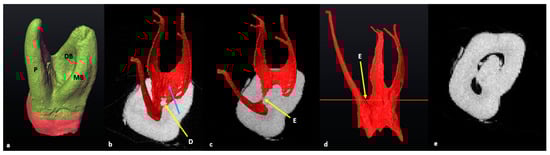

3.3. Maxillary First Molars: Three Separate Roots

3.4. Maxillary Molars: Variants in Mesial or Distal Bifurcations

3.5. Fused Roots

3.6. C-Shaped Canals